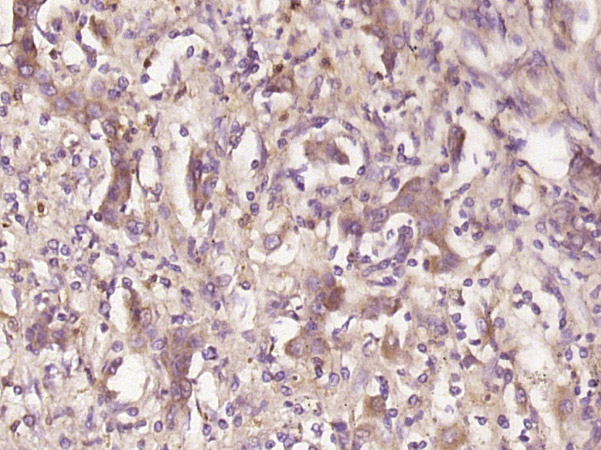

Paraformaldehyde-fixed, paraffin embedded (human liver carcinoma); Antigen retrieval by boiling in sodium citrate buffer (pH6.0) for 15min; Block endogenous peroxidase by 3% hydrogen peroxide for 20 minutes; Blocking buffer (normal goat serum) at 37°C for 30min; Antibody incubation with (Galectin 10) Polyclonal Antibody, Unconjugated (bs-13266R) at 1:400 overnight at 4°C, followed by operating according to SP Kit(Rabbit) (sp-0023) instructionsand DAB staining.

Tissue/cell: rat spleen tissue; 4% Paraformaldehyde-fixed and paraffin-embedded; Antigen retrieval: citrate buffer ( 0.01M, pH 6.0 ), Boiling bathing for 15min; Block endogenous peroxidase by 3% Hydrogen peroxide for 30min; Blocking buffer (normal goat serum,C-0005) at 37℃ for 20 min; Incubation: Anti-Galectin 10 Polyclonal Antibody, Unconjugated(bs-13266R) 1:200, overnight at 4°C, followed by conjugation to the secondary antibody(SP-0023) and DAB(C-0010) staining